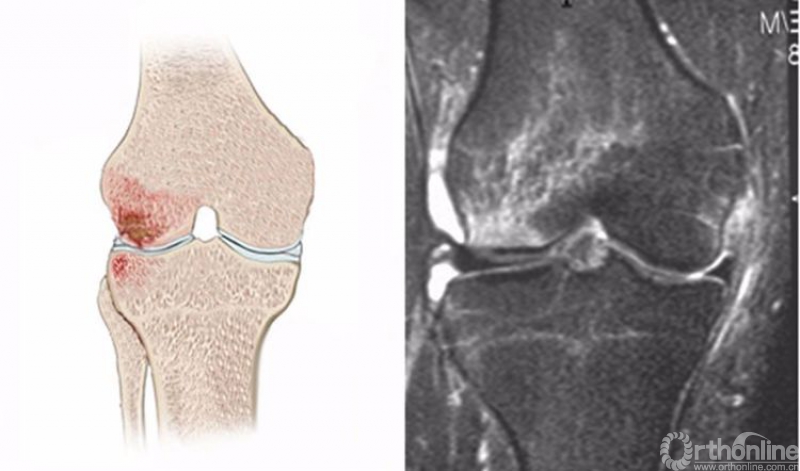

4.剪切伤(clip injury)

剪切伤是一个直接接触伤,当膝关节中度屈曲(10°–30°)时受到一个纯粹的外翻力作用所致,多见于美式橄榔球运动。

膝关节剪切伤在MRI上主要表现为股骨外侧髁、股骨内侧髁甚至胫骨外侧平台的骨髓水肿,T2WI及STIR像也呈高信号改变,又称为剪刀征(clip sign),水肿以股骨外侧髁最明显,其次是股骨内侧髁的内侧副韧带附着点,是由于受到外翻力作用而使内侧副韧带的撕脱所致,如出现胫骨外侧平台骨髓水肿则为挤压所致。可合并内侧副韧带的不同程度撕裂、前交叉韧带撕裂、内侧半月板撕裂。